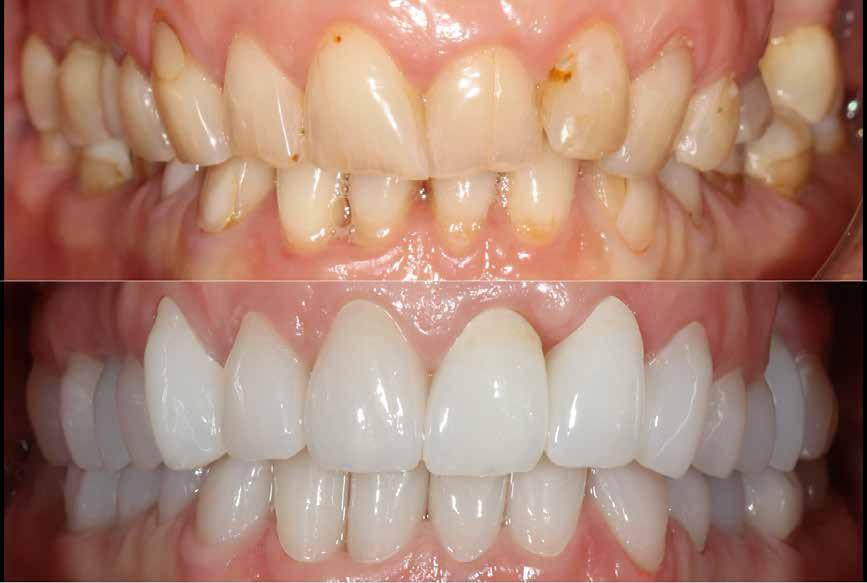

Ebben a cikkben egy olyan esetet ismertetünk, ahol a kezelés során alkalmazott munkafolyamatokat digitálisan végeztük el. Minimál-invazív preparációt követően – digitális mosolytervezés alapján – lithium-diszilikát tömbökből monolitikus héjakat és koronákat készítettünk CAD/CAM technológia felhasználásának segítségével. Az elkészült restaurátumok segítségével helyreállítottuk az elvesztett harapási magasságot, valamint megszüntettük az ebből adódó esztétikai hátrányokat és az emiatt kialakult temporomandibuláris ízületi diszfunkciót.

A koronákat (1.3-1.1 és 2.1-2.3) és a héjakat (1.7-1.4, 2.4–2.7, 3.7-3.1, 4.1–4.7) fényrekötő adhezív rendszerrel rögzítették a pillérfogakhoz (Futurabond U ésBifix QM, VOCO). A polimerizációhoz egy nagy teljesítményű LED polimerizációs lámpát használtak (Celalux 3, VOCO), (1112. ábrák).

A kifolyó ragasztóanyagot ezt követően eltávolították, majd az okklúziót a T-Scantechnológia (Tekscan) segítségével ellenőrizték, majd a szükséges mértékben korrigálták. A véglegesen rögzített kerámiapótlás védelme érdekében a páciensnek a továbbiakban egy kivehető, átlátszó műanyag fogvédő sínt kellett viselnie. A pótlásokat 6 hónap múlva ellenőrizték. Az át adott fogpótlások stabilan rögzültek, és nem találtunk sérülésekre, repedésekre utaló jeleket (13-15. ábrák). A páciens arról is beszámolt, hogy a harapás megemelése óta megszűntek az őt rendszeresen gyötrő fejfájásai.